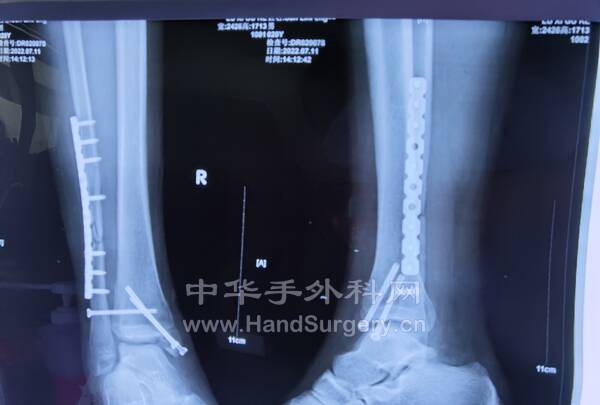

2.右跟骨闭合骨折切开复位钛板内固定术:取足跟外侧改良L形切口,逐层切开显露,剥离骨膜,显露骨折端,见距下关节变形,恢复跟骨高度,宽度及距下关节面,术中拍片示贝氏角,关节面角至正常范围,放置跟骨钛板1枚及螺钉9枚,逐层闭合切口,放置引流条2枚。